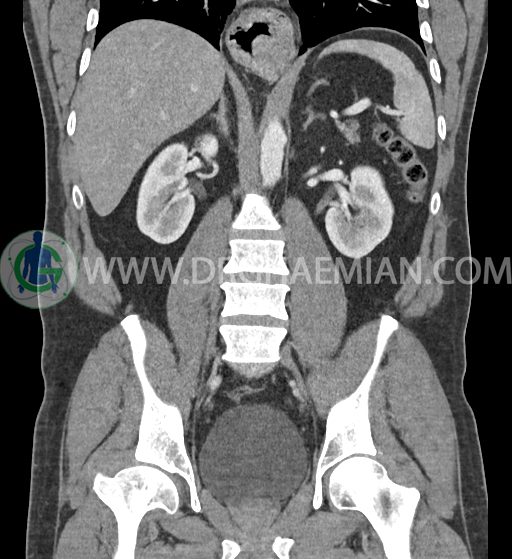

سی تی اسکن شکم و لگن با استفاده از اشعات ایکس تصاویر عرضی از ناحیه شکم و لگن ایجاد میکند. در این کیس فتق هیاتوس و هیدرویورترونفروز دیده می شود.

در سی تی اسکن اسپیرال شکم و لگن با کنتراست خوراکی و وریدی (مولتی دیدکتور 16 با مقاطع ظریف و بازسازی های ساژیتال و کرونال) :

ضایعه ای در کبد، کیسه صفرا، مجاری صفراوی، طحال، کلیه ها، پانکراس و آدرنالها مشهود نیست.

کلیه ها کنتراست را ترشح کرده اند و نمای سیستم پیلوکالیسیل و حالب دو طرف نرمال است .

-sliding hiatal hernia به ابعاد 60x44mm با جابجایی JE.junction و فوندوس معده به فضای مدیاستن خلفی دیده می شود.

-هیدرویورترونفروز جزئی دو طرفه دیده می شود که می تواند ثانویه به اتساع مثانه باشد.